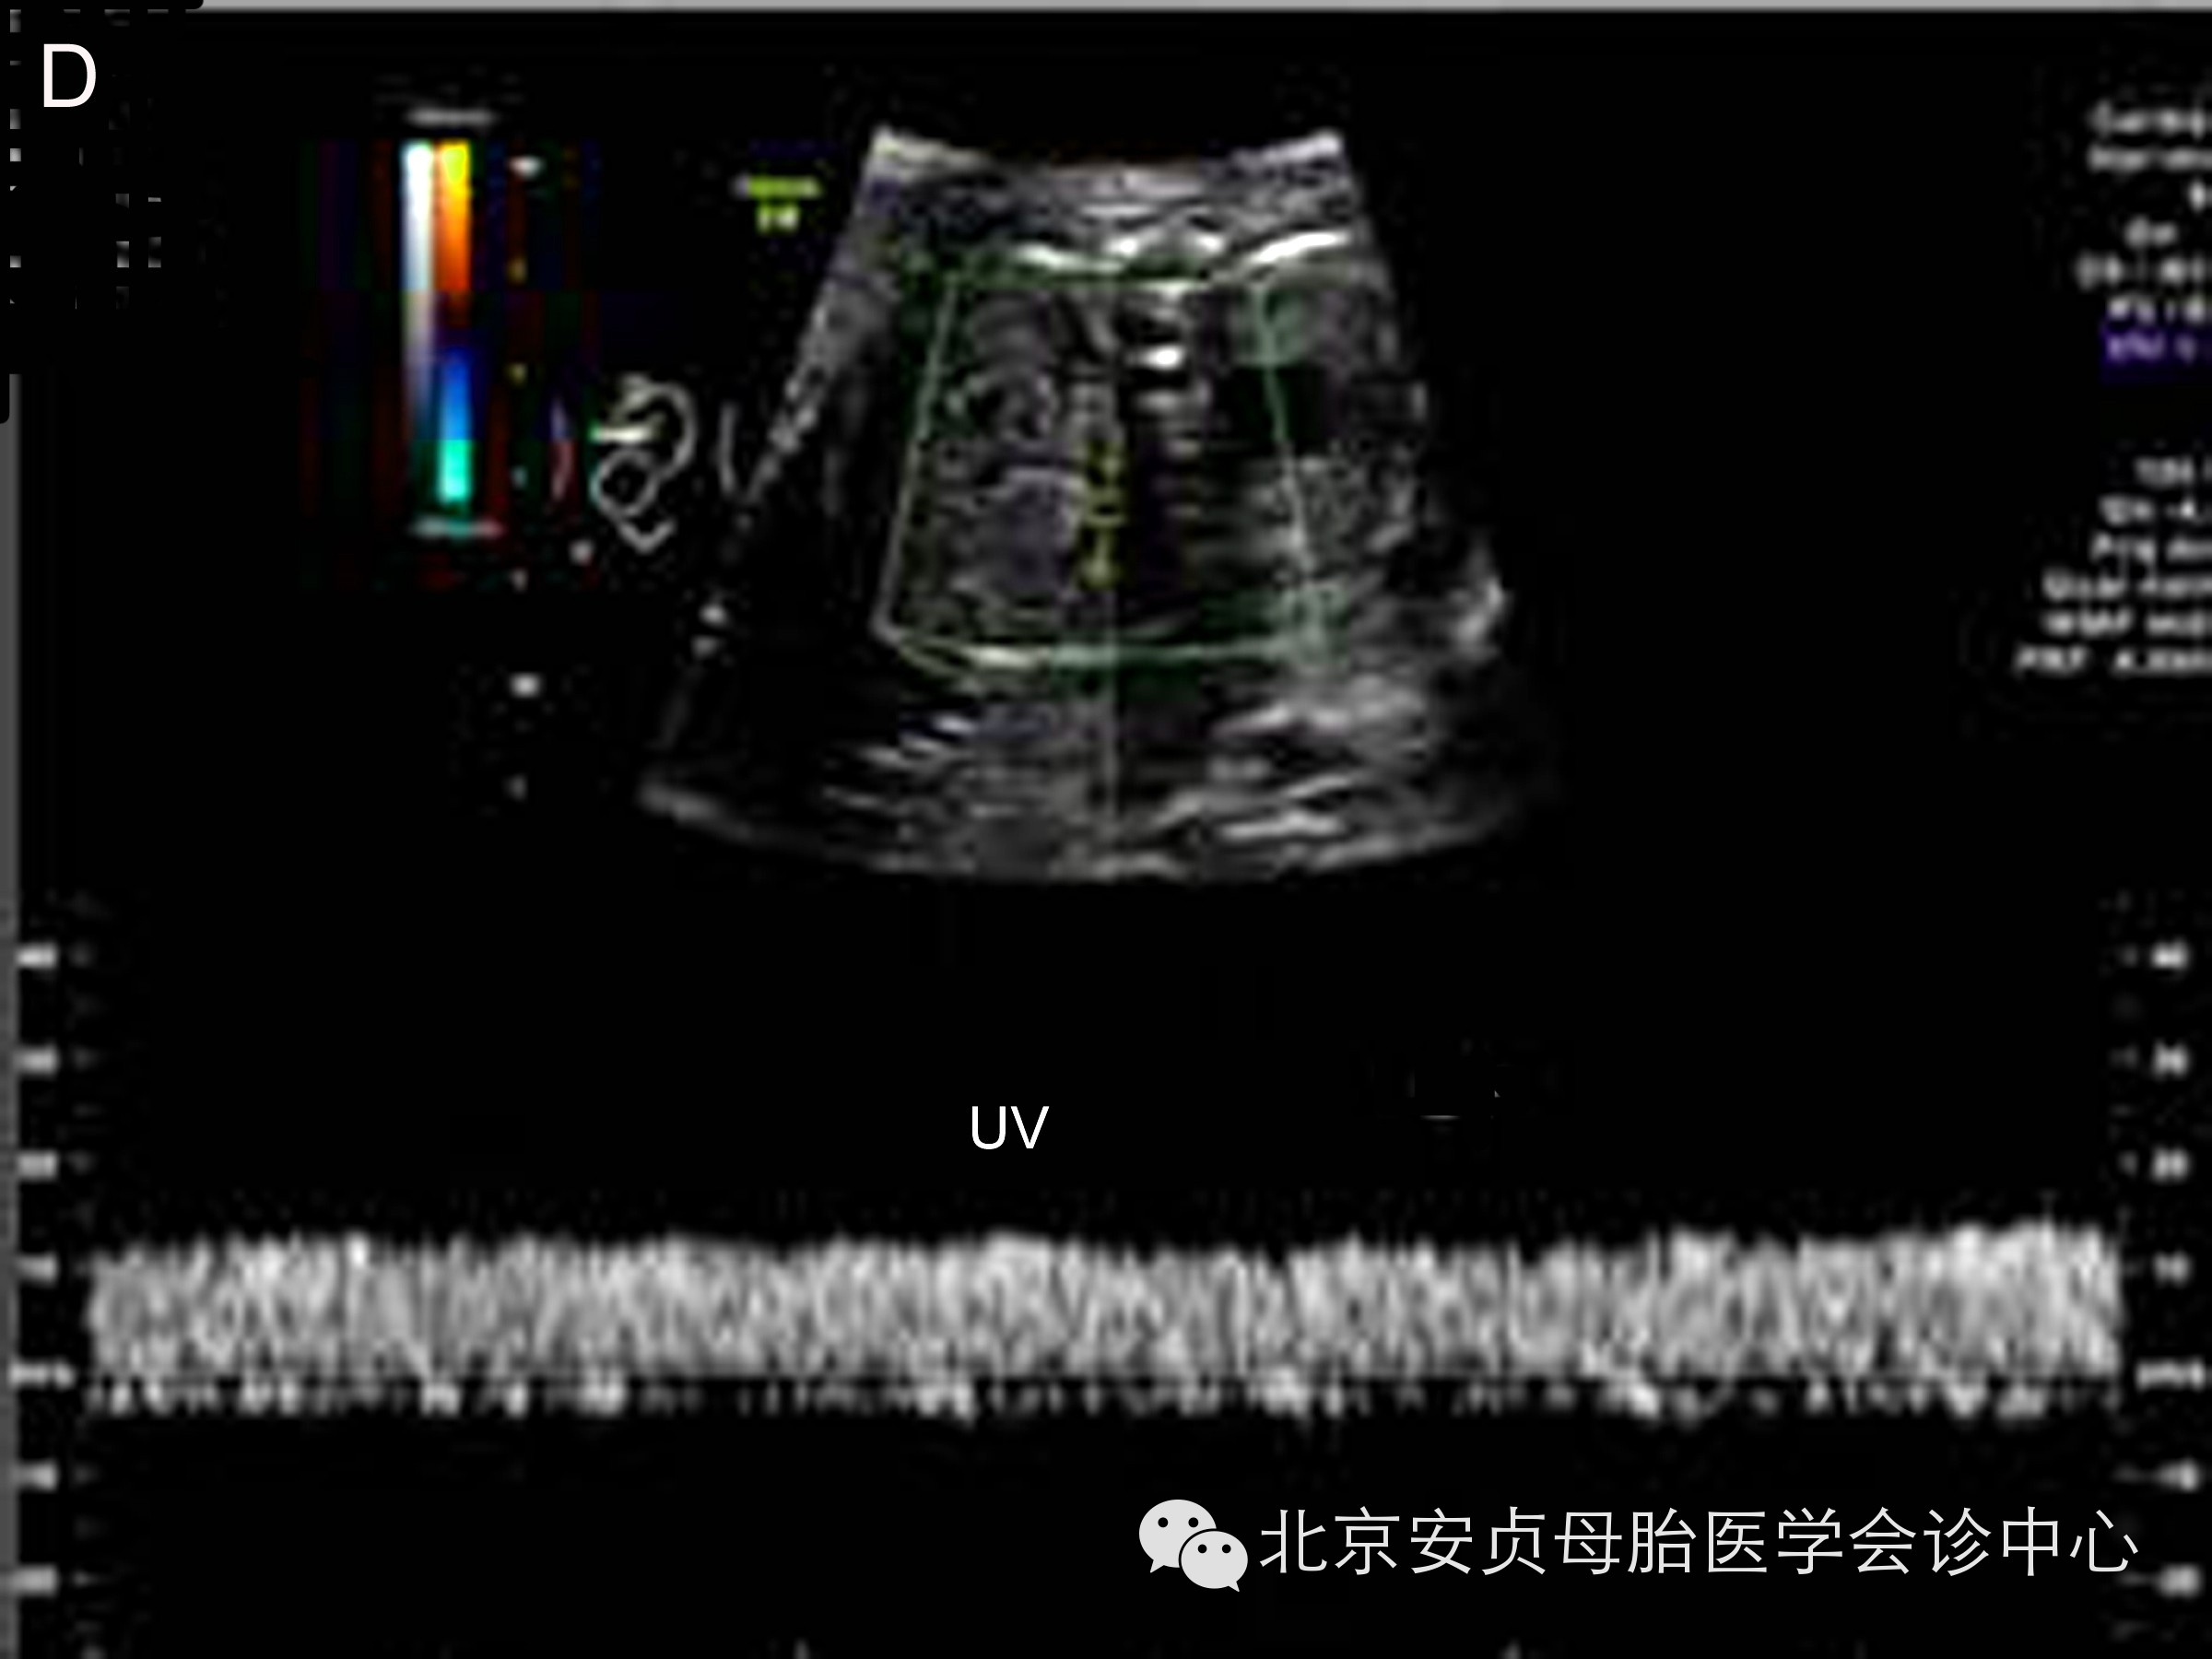

胎儿静脉血流能够客观、非特异性的用于评价心脏功能。对静脉系统频谱波形的分析主要包括:近心水平的静脉导管、下腔静脉、肝静脉、肺静脉;远心水平的腹内段脐静脉。与心房紧密相关的近心端静脉血流频谱正常均表现为多相血流波形。远心端脐静脉表现为无波动性的、低阻力连续静脉频谱波形。当上述静脉系统波形异常时,表明胎儿心脏舒张或收缩功能异常、心脏后负荷增加。

胎儿心功能不全除包括心室收缩或舒张功能减低,以下征象的出现也表明胎儿心力衰竭:心脏扩大、房室瓣反流、静脉血流频谱异常、心脏输出量重新分配(大脑中动脉舒张期血流速度增快和搏动指数减低、脐动脉舒张期血流消失或呈反向波)、胎儿水肿,如病例4,胎儿收缩功能常规测量值方面显示正常,但综合和表现提示胎儿右心功能减低。